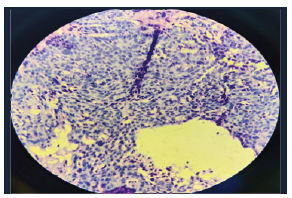

Magnetic resonance imaging (MRI) of the PNS and orbits (Figure 3) demonstrated an ill-defined, fusiform, t2 hypointense lesion with homogeneous enhancement involving the medial rectus muscle, with extensions suggestive of a pseudotumour The patient underwent endoscopic sinus surgery with excision of the intraorbital mass via Denker’s approach under general anaesthesia.3,4 The orbital mass was removed in toto and submitted for histopathological examination, which revealed features consistent with hyalohyphomycosis (Figure 4).

Postoperatively, the patient was started on antifungal therapy with itraconazole, and nasal saline irrigation was done. The patient underwent endoscopic sinus surgery with excision of the intraorbital mass via Denker’s approach under general anaesthesia.3,4 The orbital mass was removed in toto and submitted for histopathological examination, which revealed features consistent with hyalohyphomycosis (Figure 4).